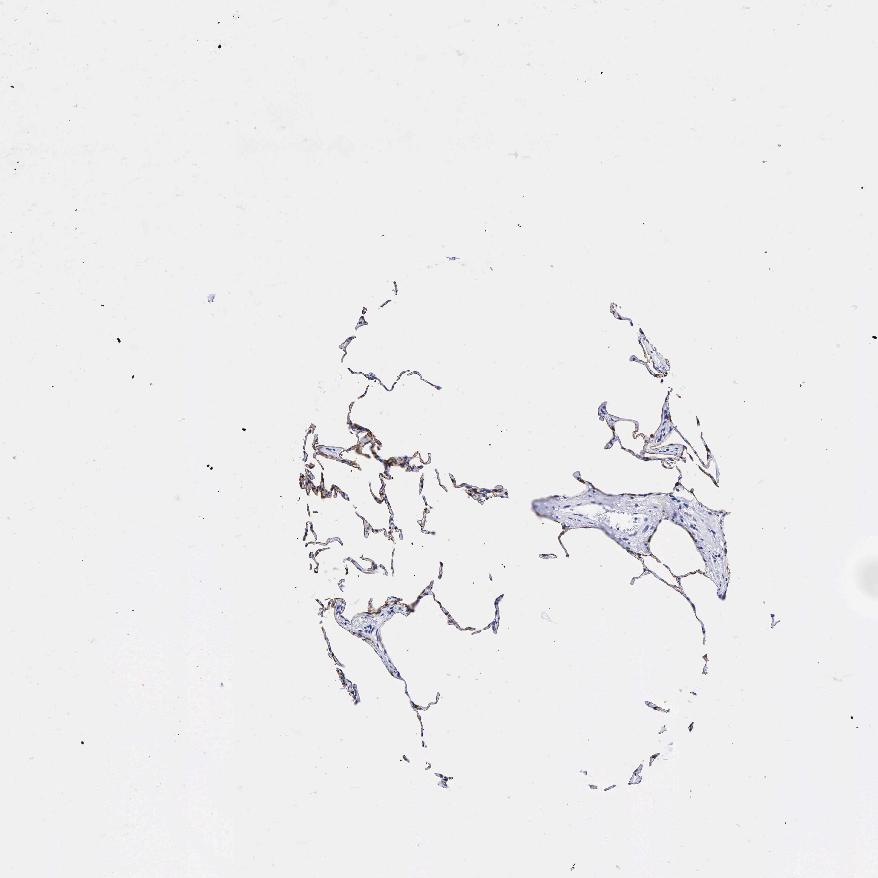

LUNG - Antibody stainingi

Antibody staining in the annotated cell types in the current human tissue is reported as not detected, low, medium, or high, based on conventional immunohistochemistry profiling in selected tissues. This score is based on the combination of the staining intensity and fraction of stained cells.

Each image is clickable and will lead to virtual microscopy that enables deeper exploration of all samples and also displays staining intensity scores, fraction scores and subcellular localization as well as patient and tissue information for each sample.

Antibody HPA002465Antibody CAB000031

Alveolar cells -High

Alveolar cells type I High-

Alveolar cells type II High-

Endothelial cells Not detected-

Macrophages Not detectedNot detected